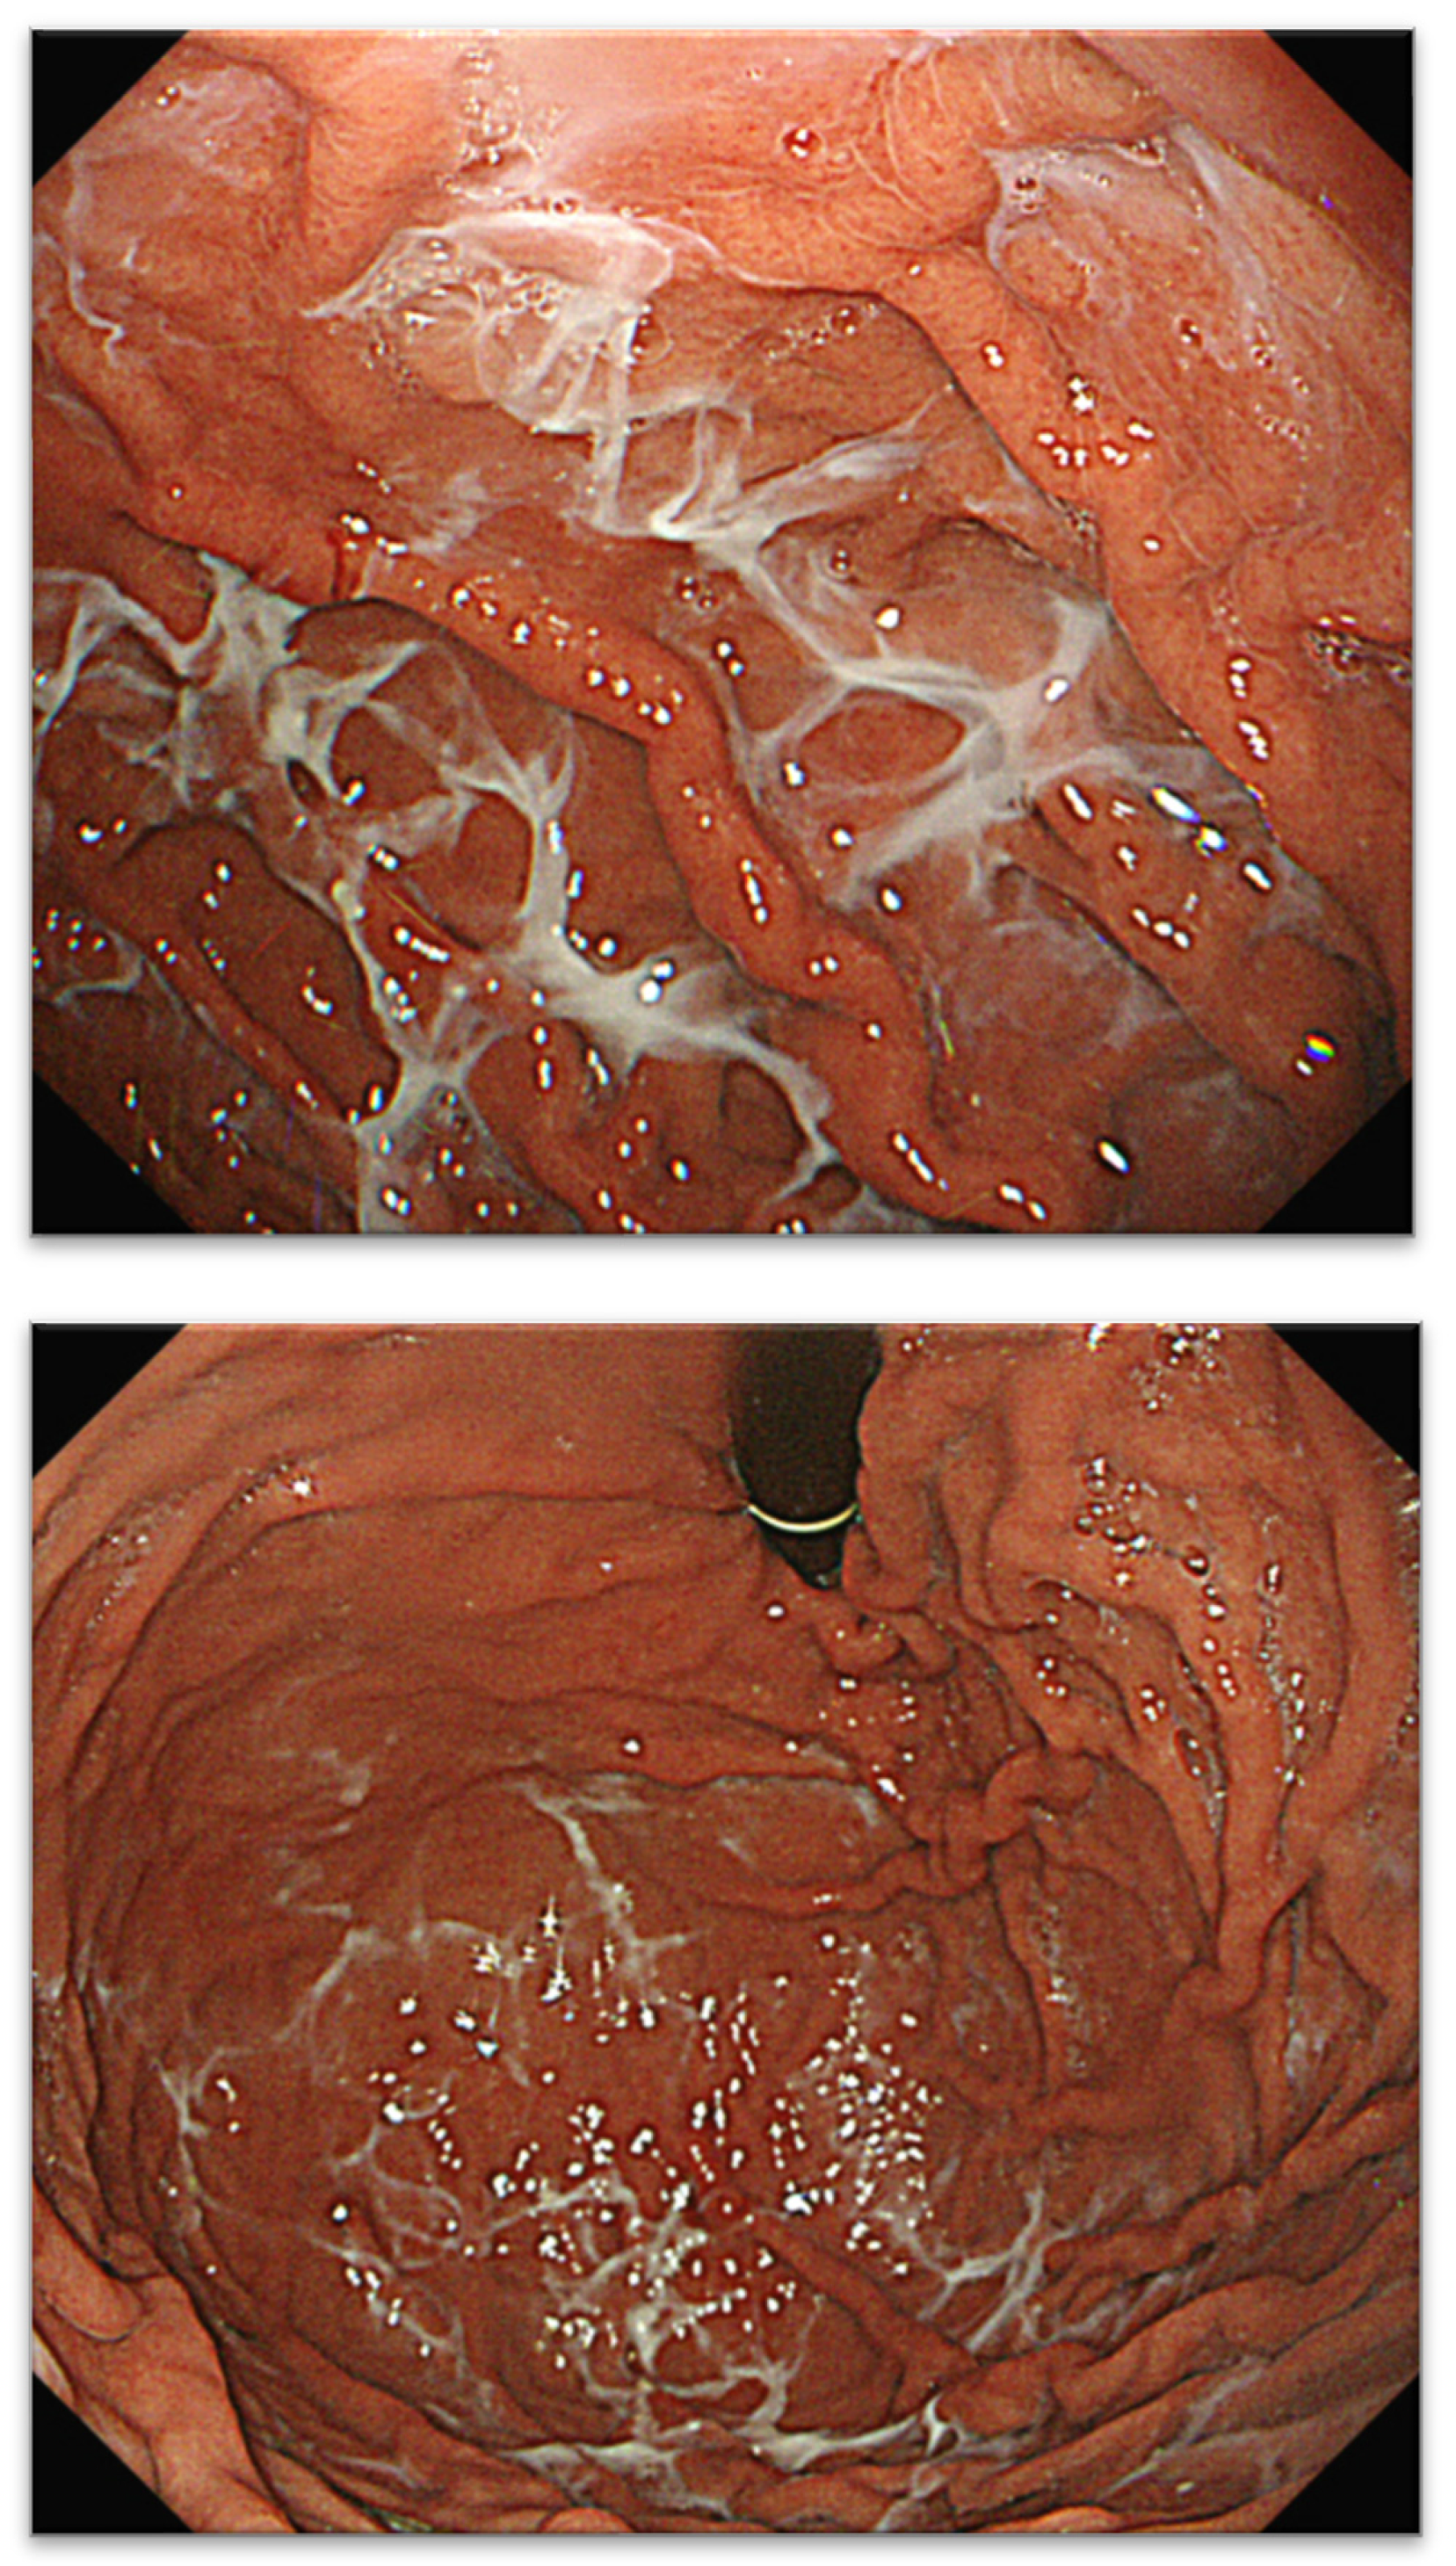

A Novel Characteristic Gastric Mucus Named “Web-like Mucus” Potentially Induced by Vonoprazan

2.1. Definitions of Web-like Mucus